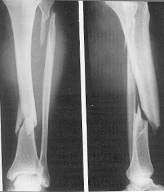

SARCOMUL EWING

Se localizeaza la nivelul oaselor lungi, cu predilectie în portiunea medie a diafizei.

Aspectul radiologic în stadiul incipient nu este caracteristic. Apar zone de osteoliza în compacta diafizara a oaselor lungi cu diametrul în jur de 1 cm. Ulterior diafiza se îngroasa fuziform, tumora se extinde, distruge corticala apoi dezlipeste periostul producâd periostoza sub forma unor lame suprapuse. Prima lama osoasa din apropierea corticalei este strapunsa de tumora formându-se o a doua lama de periostoza si asa mai departe astfel ca osul apare înconjurat de lamele osoase suprapuse asemanatoare foilor de ceapa

În stadiul avansat, corticala este partial distrusa, osul este deformat, cu contururi fluu; tumora invadeaza partile moi, se pot produce fracturi.